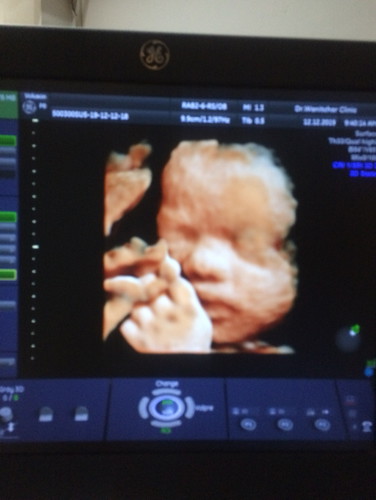

อิจจังเลยค่ะ วันนี้มาซาวด์ 4 มิติ น้องไม่ยอมหงายหน้า 😭 แถมเครื่องที่ คลินิค มีปัญหา ลุ้นมากกเลยค่ะตอนนี้

สรุปได้แค่ด้านข้าง 😂 25+3 วีค นน 700 กว่า ตามเกณฑ์ค่ะ แม่ต้องเดินขยับท้องตั้งนานกว่าได้หงายข้างมาให้เห็น 😂